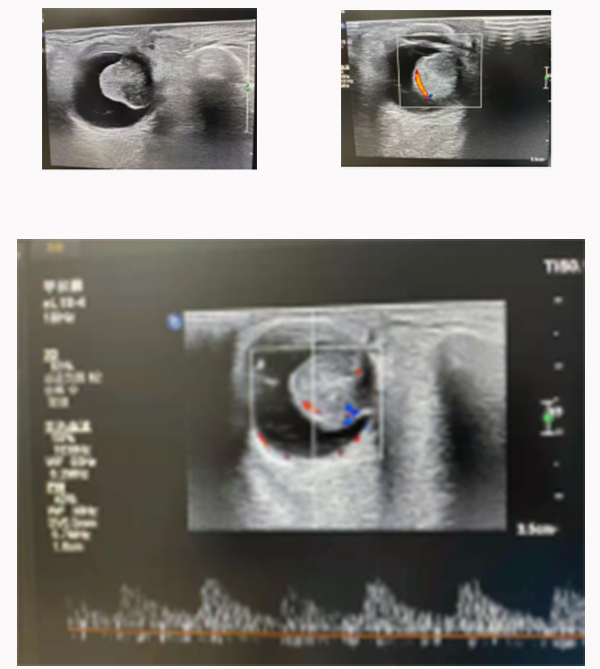

上圖是1例脈絡(luò)膜黑色素瘤患者,彩超檢查:可探及球內(nèi)隆起實(shí)性病變,邊界清晰,內(nèi)回聲不均勻?yàn)橹械突芈暎诳照?+)。CDFI:玻璃體內(nèi)病變中可探及較豐富的血流信號(hào),脈沖多普勒為動(dòng)脈型血流頻譜